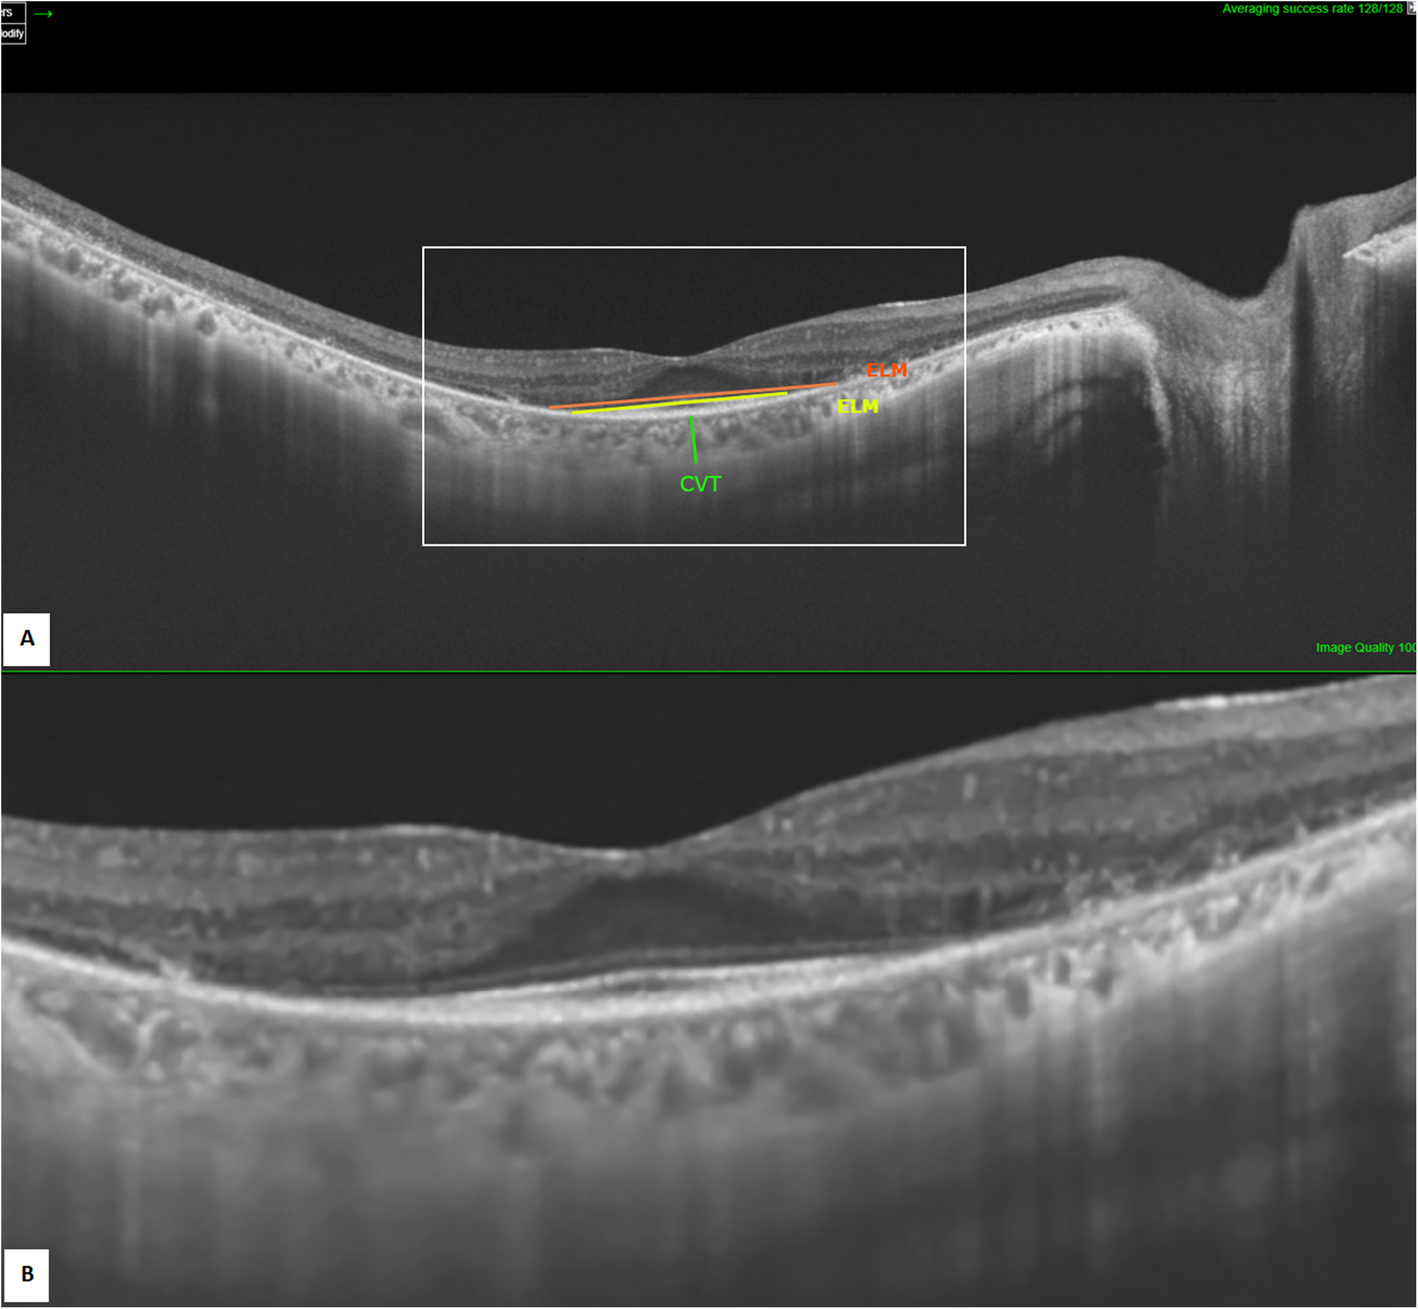

Fig. 1

SS-OCT image of the right eye (A: annotated scan, B: magnified unannotated scan) showing measurement of EZ (in yellow), ELM (in orange), and subfoveal CVT (in green)